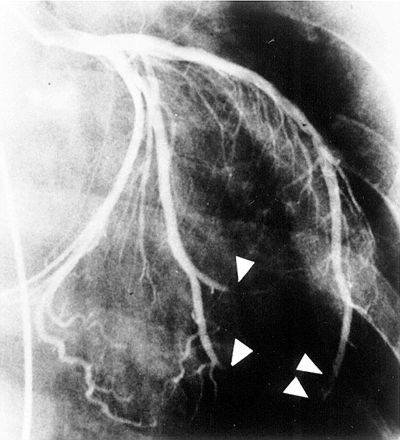

A myocardial infarct is an area of necrosis resulting from a sudden insufficiency of arterial or venous blood supply to the heart's muscular wall.- What arteries of the heart are most commonly occluded? Why do occlusions rapidly lead to infarct in the heart?

The anterior interventricular branch of the left coronary artery, the right coronary artery, and the circumflex branch of the left coronary artery. The arteries are functionally end arteries. Each major artery leads to a specific region of cardiac muscle with little to no overlap. In the heart, major collateral blood supply is lacking. Thus, occlusion of a coronary artery will have major and devastating effects on the tissue it normally supplies.- The patient decides to undergo elective CABG (pronounced "cabbage," stands for coronary artery bypass graft) surgery. What is a bypass, and why is it done?

A bypass is a shunt. The internal thoracic artery or vein grafts are used to shunt blood from the aorta to branches of the coronary arteries beyond the occlusion, "bypassing" the obstructed area to reestablish blood flow.